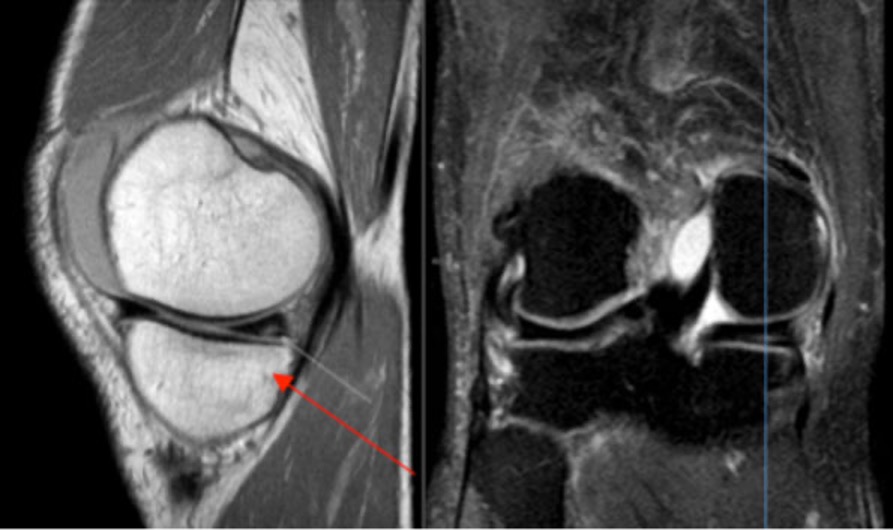

Die von den Patienten angegebenen Beschwerden sind oftmals typisch. Es wird eine schmerzhafte Bewegungseinschränkung bemerkt, welche mit einer «Einklemmungserscheinung» oder einem «Blockadephänomen» einhergeht. Ebenso charakteristisch sind ein Druckschmerz über dem Gelenkspalt und das Ausbilden eines Gelenkergusses. Im Rahmen der klinischen Untersuchung des Kniegelenkes kann durch entsprechende Bewegungsmanöver Stress auf den Meniskus ausgeübt werden, Neben den Schmerzen führt der Meniskusschaden dazu, dass sich die Knorpellagen an den Knochenenden des Oberschenkels und Schienbeins schneller abnutzen, es somit frühzeitig zu Verschleisserscheinung, also zu einer Arthrose kommt. Als Mittel der Wahl bei der bildgebenden Diagnostik ist die Magnetresonanztomographie (MRT) zu nennen. Hier kann die Verdachtsdiagnose eines Meniskusschadens mit einer Genauigkeit von etwa 95% erhärtet werden.

MRI-Bildgebung des Kniegelenks. Der rote Pfeil markiert die Meniskusläsion.